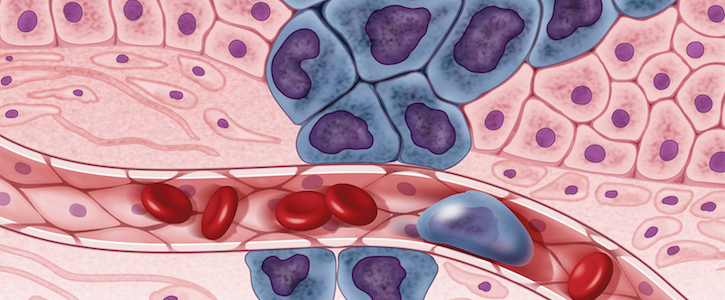

A new deal between Adventist Health and CancerIQ will make it easier for physicians to identify patients with increased genetic risk of cancer.

Adventist Health, a California-based health system, is putting cancer risk prediction tools at the fingertips of every one of its providers.

The health system, which serves 80 communities on the West Coast and in Hawaii, has signed a deal to expand its partnership with CancerIQ by integrating the cancer risk-assessment tool directly into Adventist Health’s electronic health record (EHR) system. The move is designed to streamline the way the health system identifies patients at a significant genetic risk of cancer and help providers manage next steps to prevent or diagnose the disease in such patients.

CancerIQ works by integrating key patient data like family history and integrating it with National Comprehensive Cancer Network (NCCN) guidelines and predictive analytics models. About 10% of new cancer diagnoses are for hereditary cancers. Patients at a high risk for genetic cancers can take steps large and small to avoid cancer or mitigate the risk, including through genetic testing and even preventive mastectomies. However, such steps can only be taken if the patient knows their risk profile.